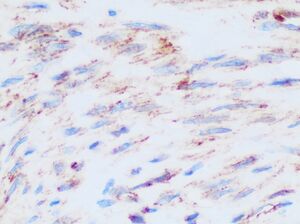

β-Catenin is a proto-oncogene. Mutations of this gene are commonly found in a variety of cancers: in primary hepatocellular carcinoma, colorectal cancer, ovarian carcinoma, breast cancer, lung cancer and glioblastoma. It has been estimated that approximately 10% of all tissue samples sequenced from all cancers display mutations in the CTNNB1 gene.[73] Most of these mutations cluster on a tiny area of the N-terminal segment of β-catenin: the β-TrCP binding motif. Loss-of-function mutations of this motif essentially make ubiquitinylation and degradation of β-catenin impossible. It will cause β-catenin to translocate to the nucleus without any external stimulus and continuously drive transcription of its target genes. Increased nuclear β-catenin levels have also been noted in basal cell carcinoma (BCC),[74] head and neck squamous cell carcinoma (HNSCC), prostate cancer (CaP),[75] pilomatrixoma (PTR)[76] and medulloblastoma (MDB)[77] These observations may or may not implicate a mutation in the β-catenin gene: other Wnt pathway components can also be faulty.

- ^ Carlson JW, Fletcher CD (October 2007). "Immunohistochemistry for beta-catenin in the differential diagnosis of spindle cell lesions: analysis of a series and review of the literature". Histopathology. 51 (4): 509–514. doi:10.1111/j.1365-2559.2007.02794.x. PMID 17711447. Archived from the original on March 25, 2024.